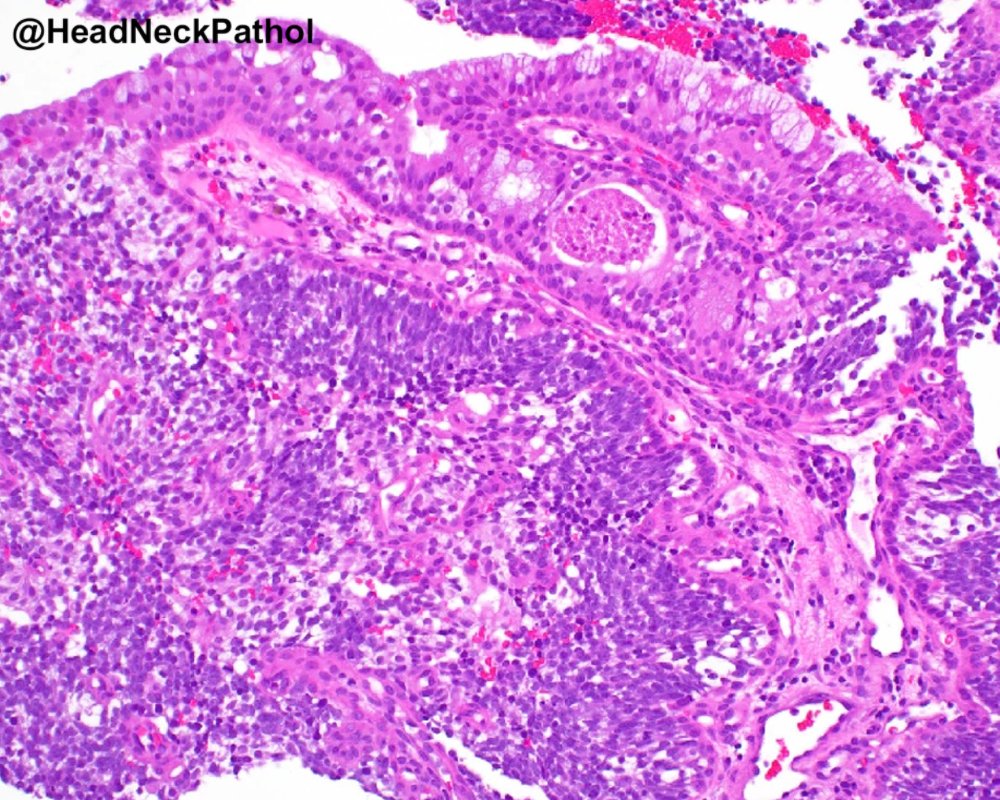

Characterization of CD8 + & CD68 + Microenvironment & PDL1 Expression in HPV-related Multiphenotypic Sinonasal Carcinoma

Silva de Araújo, Gonçalves de Paiva, Lima Fernandes, et al.